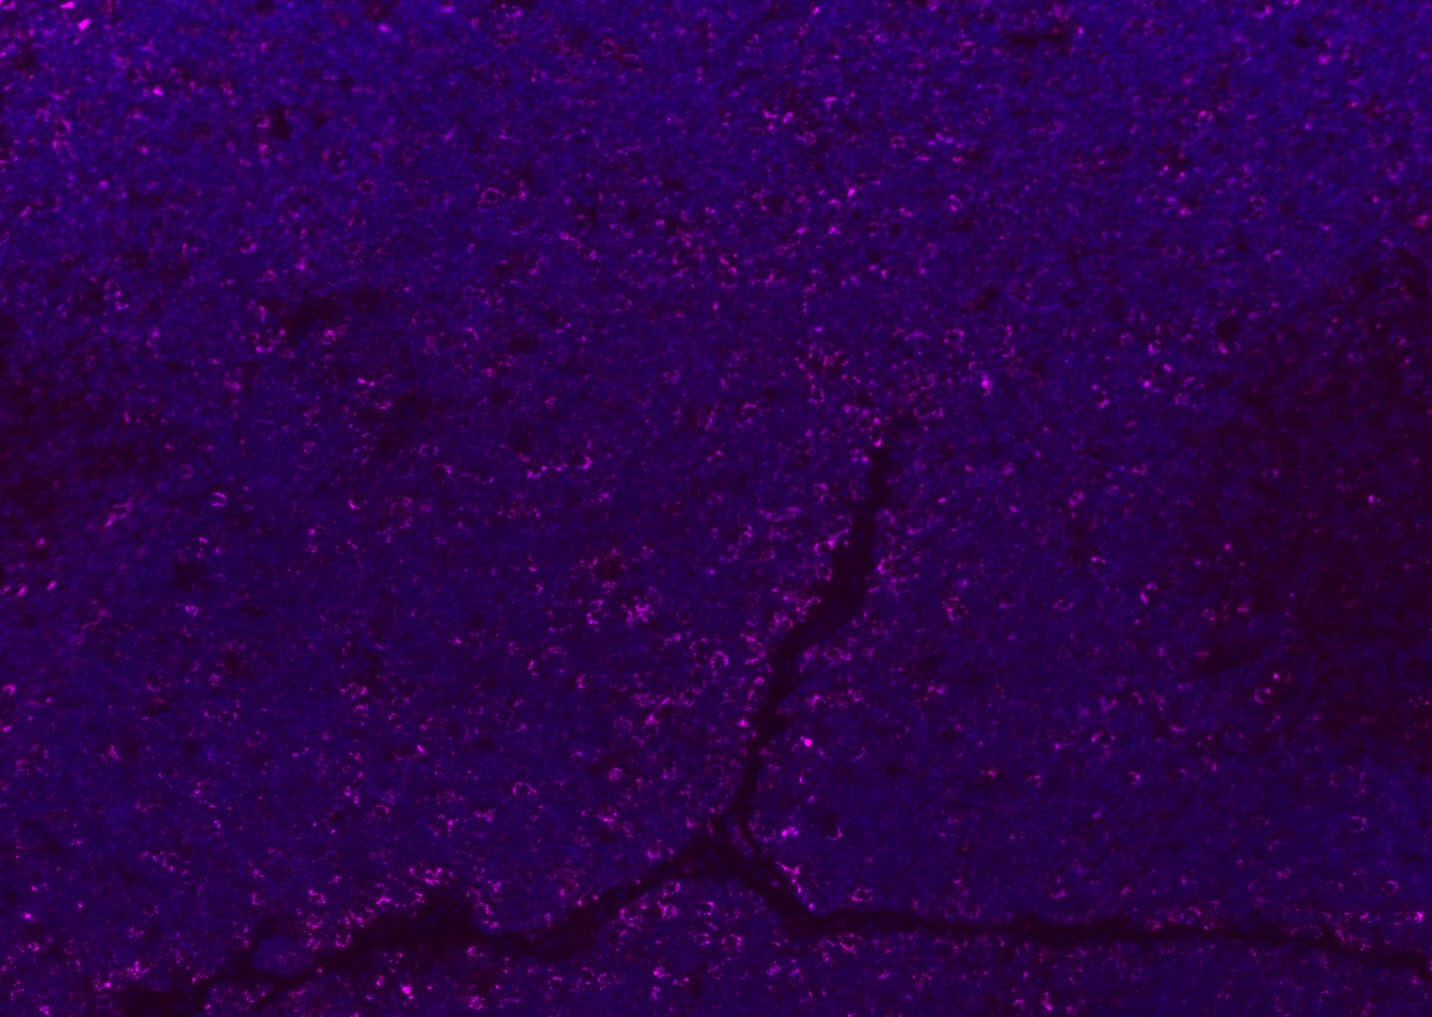

| Verified Activity | 1. Tissue/cell: human lung carcinoma;4% Paraformaldehyde-fixed and paraffin-embedded; Antigen retrieval: citrate buffer (0.01M, pH6.0), Boiling bathing for 15 min; Blocking buffer (normal goat serum) at 37°C for 20 min; Incubation: Anti-CD8 Polyclonal Antibody, Unconjugated (TMAB-00392) 1:200, overnight at 4°C; The secondary antibody was Goat Anti-Rabbit IgG, Cy3 conjugated used at 1:200 dilution for 40 minutes at 37°C. DAPI (5 μg/ml,blue) was used to stain the cell nucleus. 2. Paraformaldehyde-fixed, paraffin embedded (mouse lymphoid); Antigen retrieval by boiling in sodium citrate buffer (pH6.0) for 15 min; Blocking buffer (normal goat serum) at 37°C for 30 min; Antibody incubation with (CD8B) Polyclonal Antibody, Unconjugated (TMAB-00392) at 1:200 overnight at 4°C, followed by a conjugated Goat Anti-Rabbit IgG antibody for 90 minutes, and DAPI for nucleus staining. 3. Paraformaldehyde-fixed, paraffin embedded (rat spleen); Antigen retrieval by boiling in sodium citrate buffer (pH6.0) for 15 min; Blocking buffer (normal goat serum) at 37°C for 30 min; Antibody incubation with (CD8B) Polyclonal Antibody, Unconjugated (TMAB-00392) at 1:200 overnight at 4°C, followed by a conjugated Goat Anti-Rabbit IgG antibody for 90 minutes, and DAPI for nucleus staining. 4. Paraformaldehyde-fixed, paraffin embedded (mouse thymus); Antigen retrieval by boiling in sodium citrate buffer (pH6.0) for 15 min; Blocking buffer (normal goat serum) at 37°C for 30 min; Antibody incubation with (CD8B) Polyclonal Antibody, Unconjugated (TMAB-00392) at 1:200 overnight at 4°C, followed by a conjugated Goat Anti-Rabbit IgG antibody for 90 minutes, and DAPI for nucleus staining. 5. Paraformaldehyde-fixed, paraffin embedded (rat lymphoid); Antigen retrieval by boiling in sodium citrate buffer (pH6.0) for 15 min; Blocking buffer (normal goat serum) at 37°C for 30 min; Antibody incubation with (CD8B) Polyclonal Antibody, Unconjugated (TMAB-00392) at 1:200 overnight at 4°C, followed by a conjugated Goat Anti-Rabbit IgG antibody for 90 minutes, and DAPI for nucleus staining. 6. Paraformaldehyde-fixed, paraffin embedded (rat thymus); Antigen retrieval by boiling in sodium citrate buffer (pH6.0) for 15 min; Blocking buffer (normal goat serum) at 37°C for 30 min; Antibody incubation with (CD8B) Polyclonal Antibody, Unconjugated (TMAB-00392) at 1:200 overnight at 4°C, followed by a conjugated Goat Anti-Rabbit IgG antibody for 90 minutes, and DAPI for nucleus staining. 7. Paraformaldehyde-fixed, paraffin embedded (human tonsil); Antigen retrieval by boiling in sodium citrate buffer (pH6.0) for 15 min; Blocking buffer (normal goat serum) at 37°C for 30 min; Antibody incubation with (CD8B) Polyclonal Antibody, Unconjugated (TMAB-00392) at 1:200 overnight at 4°C, followed by a conjugated Goat Anti-Rabbit IgG antibody for 90 minutes, and DAPI for nucleus staining. 8. Paraformaldehyde-fixed, paraffin embedded (mouse lymphoid); Antigen retrieval by boiling in sodium citrate buffer (pH6.0) for 15 min; Blocking buffer (normal goat serum) at 37°C for 30 min; Antibody incubation with (CD8B) Polyclonal Antibody, Unconjugated (TMAB-00392) at 1:200 overnight at 4°C, followed by a conjugated Goat Anti-Rabbit IgG antibody for 90 minutes, and DAPI for nucleus staining. 9. Paraformaldehyde-fixed, paraffin embedded (rat thymus); Antigen retrieval by boiling in sodium citrate buffer (pH6.0) for 15 min; Blocking buffer (normal goat serum) at 37°C for 30 min; Antibody incubation with (CD8B) Polyclonal Antibody, Unconjugated (TMAB-00392) at 1:200 overnight at 4°C, followed by a conjugated Goat Anti-Rabbit IgG antibody for 90 minutes, and DAPI for nucleus staining. 10. Paraformaldehyde-fixed, paraffin embedded (human tonsil); Antigen retrieval by boiling in sodium citrate buffer (pH6.0) for 15 min; Blocking buffer (normal goat serum) at 37°C for 30 min; Antibody incubation with (CD8B) Polyclonal Antibody, Unconjugated (TMAB-00392) at 1:200 overnight at 4°C, followed by a conjugated Goat Anti-Rabbit IgG antibody for 90 minutes, and DAPI for nucleus staining. 11. Paraformaldehyde-fixed, paraffin embedded (mouse spleen); Antigen retrieval by boiling in sodium citrate buffer (pH6.0) for 15 min; Blocking buffer (normal goat serum) at 37°C for 30 min; Antibody incubation with (CD8B) Polyclonal Antibody, Unconjugated (TMAB-00392) at 1:200 overnight at 4°C, followed by a conjugated Goat Anti-Rabbit IgG antibody for 90 minutes, and DAPI for nucleus staining. 12. Paraformaldehyde-fixed, paraffin embedded (rat lymphoid); Antigen retrieval by boiling in sodium citrate buffer (pH6.0) for 15 min; Blocking buffer (normal goat serum) at 37°C for 30 min; Antibody incubation with (CD8B) Polyclonal Antibody, Unconjugated (TMAB-00392) at 1:200 overnight at 4°C, followed by a conjugated Goat Anti-Rabbit IgG antibody for 90 minutes, and DAPI for nucleus staining. 13. Paraformaldehyde-fixed, paraffin embedded (Rat lymphoid); Antigen retrieval by boiling in sodium citrate buffer (pH6.0) for 15 min; Blocking buffer (normal goat serum) at 37°C for 30 min; Antibody incubation with (CD8B) Polyclonal Antibody, Unconjugated (TMAB-00392) at 1:100 overnight at 4°C, followed by a conjugated Goat Anti-Rabbit IgG antibody for 90 minutes, and DAPI for nucleus staining. 14. Paraformaldehyde-fixed, paraffin embedded (mouse thymus); Antigen retrieval by boiling in sodium citrate buffer (pH6.0) for 15 min; Blocking buffer (normal goat serum) at 37°C for 30 min; Antibody incubation with (CD8B) Polyclonal Antibody, Unconjugated (TMAB-00392) at 1:100 overnight at 4°C, followed by a conjugated Goat Anti-Rabbit IgG antibody for 90 minutes, and DAPI for nucleus staining. 15. Paraformaldehyde-fixed, paraffin embedded (mouse spleen); Antigen retrieval by boiling in sodium citrate buffer (pH6.0) for 15 min; Blocking buffer (normal goat serum) at 37°C for 30 min; Antibody incubation with (CD8B) Polyclonal Antibody, Unconjugated (TMAB-00392) at 1:100 overnight at 4°C, followed by a conjugated Goat Anti-Rabbit IgG antibody for 90 minutes, and DAPI for nucleus staining. 16. Paraformaldehyde-fixed, paraffin embedded (rat spleen); Antigen retrieval by boiling in sodium citrate buffer (pH6.0) for 15 min; Blocking buffer (normal goat serum) at 37°C for 30 min; Antibody incubation with (CD8B) Polyclonal Antibody, Unconjugated (TMAB-00392) at 1:100 overnight at 4°C, followed by a conjugated Goat Anti-Rabbit IgG antibody for 90 minutes, and DAPI for nucleus staining. 17. Paraformaldehyde-fixed, paraffin embedded (rat thymus); Antigen retrieval by boiling in sodium citrate buffer (pH6.0) for 15 min; Blocking buffer (normal goat serum) at 37°C for 30 min; Antibody incubation with (CD8B) Polyclonal Antibody, Unconjugated (TMAB-00392) at 1:100 overnight at 4°C, followed by a conjugated Goat Anti-Rabbit IgG antibody for 90 minutes, and DAPI for nucleus staining. 18. Paraformaldehyde-fixed, paraffin embedded (human tonsil); Antigen retrieval by boiling in sodium citrate buffer (pH6.0) for 15 min; Blocking buffer (normal goat serum) at 37°C for 30 min; Antibody incubation with (CD8B) Polyclonal Antibody, Unconjugated (TMAB-00392) at 1:100 overnight at 4°C, followed by a conjugated Goat Anti-Rabbit IgG antibody for 90 minutes, and DAPI for nucleus staining. 19. Paraformaldehyde-fixed, paraffin embedded (mouse lymphoid); Antigen retrieval by boiling in sodium citrate buffer (pH6.0) for 15 min; Blocking buffer (normal goat serum) at 37°C for 30 min; Antibody incubation with (CD8B) Polyclonal Antibody, Unconjugated (TMAB-00392) at 1:100 overnight at 4°C, followed by a conjugated Goat Anti-Rabbit IgG antibody for 90 minutes, and DAPI for nucleus staining. ![]() ![]() ![]() ![]() ![]() ![]() ![]() ![]() ![]() ![]() ![]() ![]() ![]() ![]() ![]() ![]() ![]() ![]() ![]() |